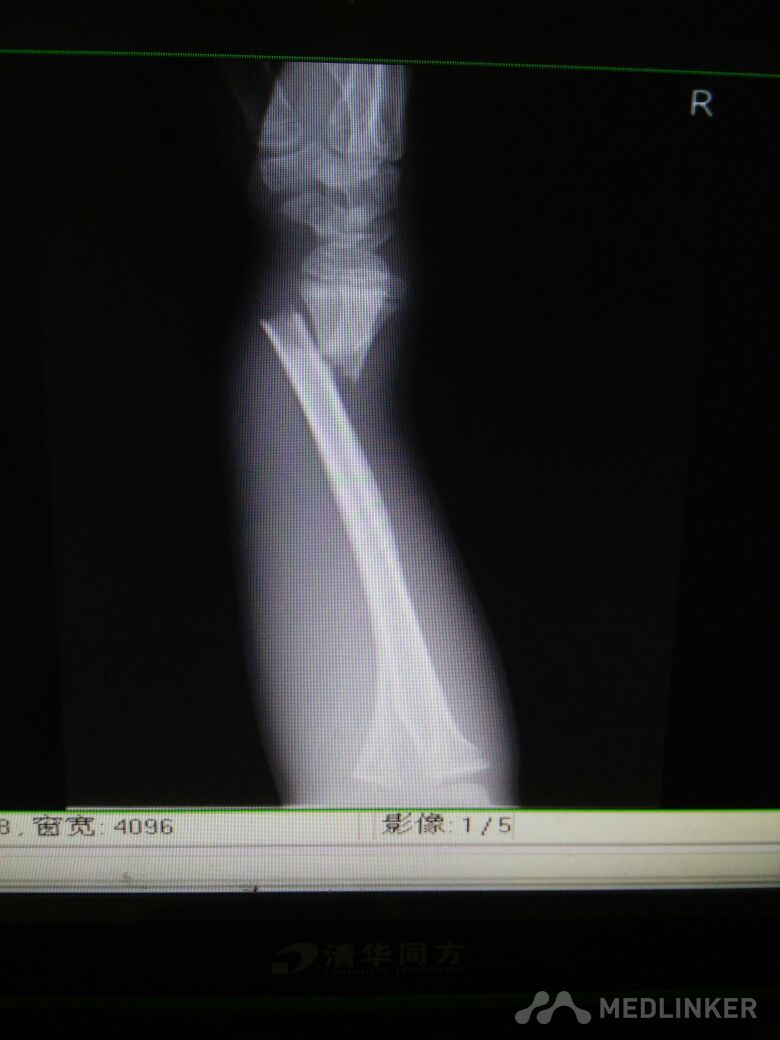

脾破裂,右尺桡骨骨折

尺桡骨骨折

病员男性,15岁。车祸伤致腹痛、右腕部畸形活动受限3小时入院,腹部B超提示:腹腔肠间隙积液,脾破裂。DR检查:右尺桡骨远端骨折。入院后行急诊剖腹探查术脾切除,右尺桡骨手法复位小夹板外固定,右腕复查对位久佳,这种还须手术切开复位吗?